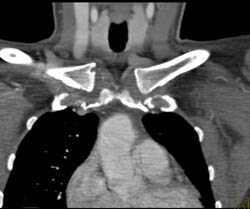

Bleed in Muscle S/P Stab Wound